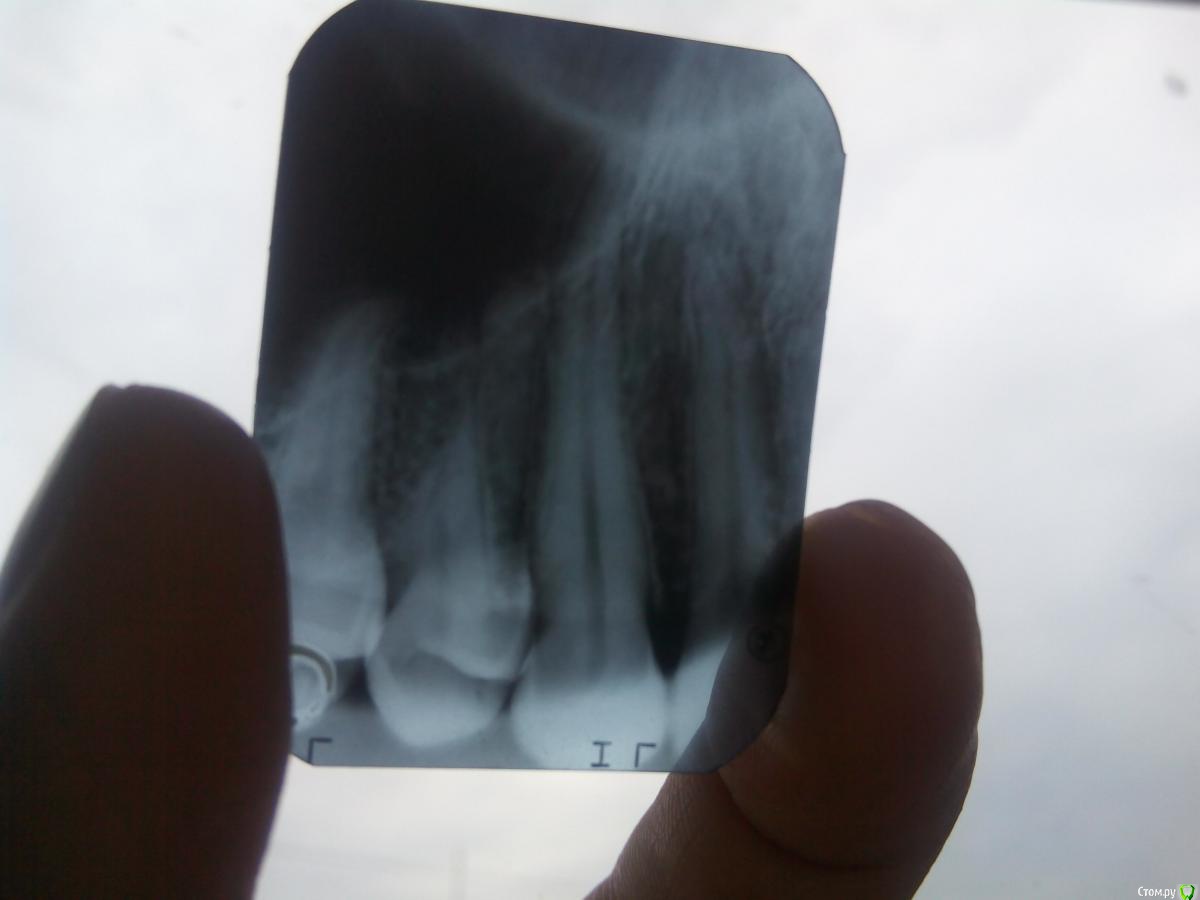

PetrBond7 Опубликовано 19 июня, 2015 Поделиться Опубликовано 19 июня, 2015 (изменено) здрасти всем, может кто что посоветует, ситуация такая.удар в зуб, разрыв щеки - опухла губа, проходит неделя, все заживает, но замечаю что зуб болит (клык) при постукивание, жевать не больно, ни на что не реагирует, начинаю прощупывать десну и понимаю что боль идёт от корня, ( как бы при нажатие на корень создаеться давление в низ в зуб (как то так)) иду к стоматологу, снимки все дела, зуб хороший, иду к другим стоматологом, все говорят вроде все хорошо... иду к лору, отправил на снимок пазух, все чисто, выписал амоксициклин, пропил 21 день, боль осталось, но теперь еще высыпало заднюю стенку горла гнойниками желто-белыми, визуально 3-4 штуки, болит одна сторона горло где и больной зуб, температура 37 ,все время послетравмы.. ( может это не имеет никакогоотношения у зубу, но все же...) все зубы пролечены, кариозных нет. Это все было 1.5 месяца назад, сегодня сделал новый снимок зуба.( на фото 3 слева вроде...)Подскажите что нить надоело уже... Изменено 19 июня, 2015 пользователем PetrBond7 Ссылка на комментарий

DmitrySH Опубликовано 19 июня, 2015 Поделиться Опубликовано 19 июня, 2015 Патологии на снимке не видно. Для полного исключения проблем с зубом - тест на витальность пульпы 1 Ссылка на комментарий